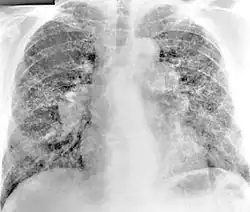

Diagnosis of berylliosis is based on history of beryllium exposures, documented beryllium sensitivity, and granulomatous inflammation on lung biopsy. Given the invasive nature of a lung biopsy, diagnosis can also be based on clinical history consistent with berylliosis, abnormal chest x-ray or CT scan findings, and abnormalities in pulmonary function tests.[15]

Chest radiography findings of berylliosis are non-specific. Early in the disease radiography findings are usually normal. In later stages interstitial fibrosis, pleural irregularities, hilar lymphadenopathy and ground-glass opacities have been reported.[19][20] Findings on CT are also not specific to berylliosis. Findings that are common in CT scans of people with berylliosis include parenchymal nodules in early stages. One study found that ground-glass opacities were more commonly seen on CT scan in berylliosis than in sarcoidosis. In later stages hilar lymphadenopathy, interstitial pulmonary fibrosis and pleural thickening.[20]